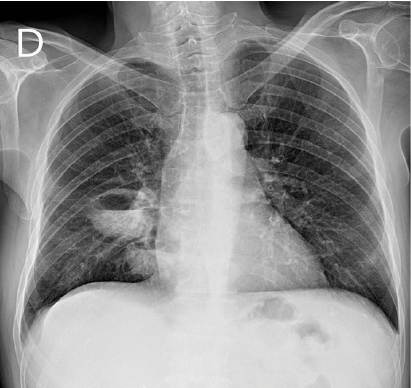

Fig. 2

Radiografía simple de tórax postero anterior. Se aprecian dos lesiones cavitadas con nivel hidroaéreo en su interior